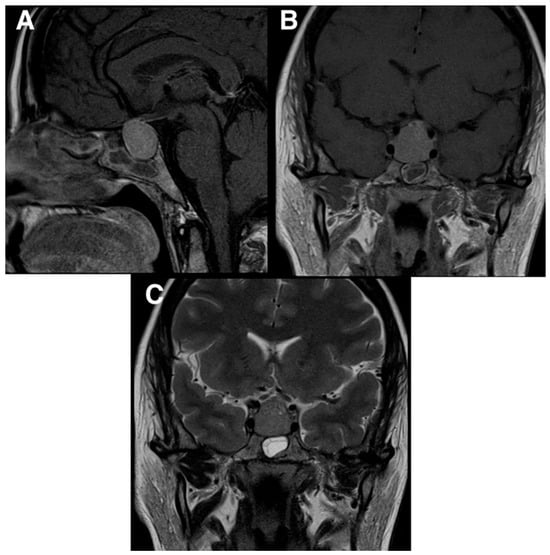

2. Case Presentation